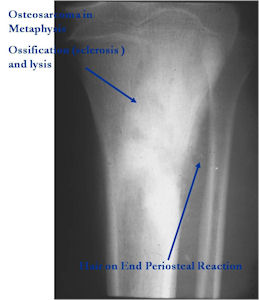

Aggressive Osteoblastoma vs. Osteosarcoma

Osteosarcoma:

- Cellular atypia

- High mitotic rate

- Atypical mitotic figures

- Abundant lacelike osteoid

- Permeative growth into adjacent bone and soft tissue

- Presence of neoplastic cartilage

- No peripheral shell of reactive bone

- Differentiation from osteosarcoma

- Osteoblastomas that are greater than 4 cm and that show prominent periosteal new bone formation may present problems in differentiation from osteosarcoma

- May have foci of lace-like osteoid, high cellularity and more than a few scattered mitotic figures but these characteristics usually occur independently in an osteoblastoma vs all these atypical characteristics being present in an osteosarcoma